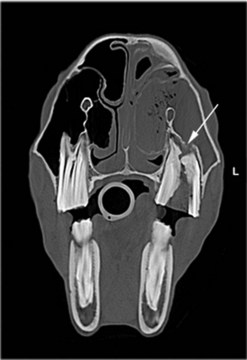

image image image

Fig. 13.43 Radiograph (A) and CT images (B and C) of a compound odontoma in a 2-year-old TB colt.

(Images courtesy of J. Easley.)